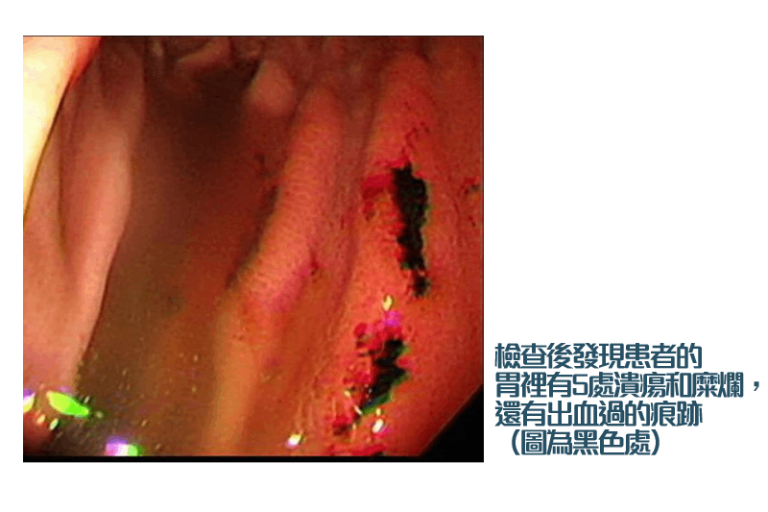

胃潰瘍是常見於繁忙都市人的疾病。胃潰瘍初期症狀可能不明顯,胃潰瘍會自己好嗎?有台灣醫生近日分享一個病例,男患者不喝咖啡,不吃甜食或零食,日常飲食清淡,惟早前因左上腹悶痛、糞便顏色比較深黑,遂去求醫始發現患有胃潰瘍。